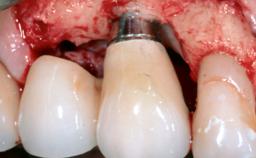

Peri-Implantitis Modified by the Presence of Submucosal Excess Cement: Reconstructive Therapy and a Ten-Year Follow-up

This case outlines the reconstructive therapy by Giovanni Salvi resulting in defect fill and inflammation-free peri-implant soft tissues at 10-year follow up. This case highlights the importance of regular monitoring of implants during supportive therapy.

A 30-year-old female patient was referred to the Department of Periodontology of the University of Bern, Switzerland, by a private dentist. Tooth 45 was congenitally missing and had been replaced with an implant three years prior to the first visit at the Department of Periodontology.